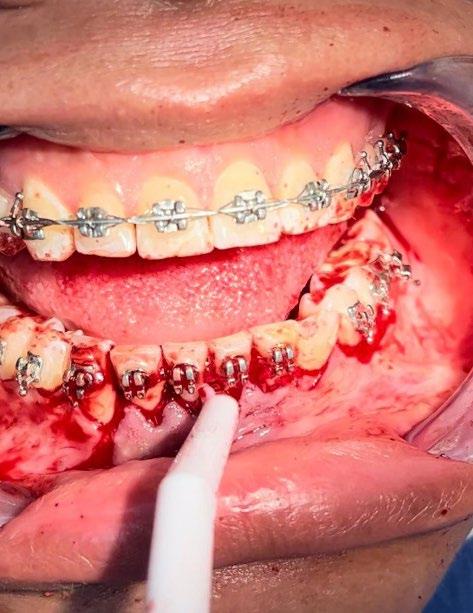

Previa asepsia y antisepsia, más colocación de campos en forma habitual, mediante infiltración troncular y de forma local, se realiza incisión

marginal con descarga lineal para levantar un colgajo seminewman (Figura 3). Se realiza ostectomía y osteotomía para liberar el órgano dentario retenido y facilitar su extracción (Figura 4). Una vez fuera de la cavidad bucal, se realiza tratamiento de conductos y obturación. De forma simultánea, se lleva a cabo la extracción atraumática del órgano dentario 73 (Figura 5) y la preparación alveolar del lecho receptor para recibir el órgano dentario a trasplantar bajo parámetros quirúrgicos (Figura 6).

En la zona postextracción del canino retenido (Figura 7), se realiza la conformación con materiales biocompatibles a base de xenoinjerto bovino y membrana de colágeno, para favorecer la correcta reparación de los tejidos blandos y duros, dadas las dimensiones del probable defecto, finalizando con sutura absorbible Vicryl 3-0 (Figuras 8 y 9).